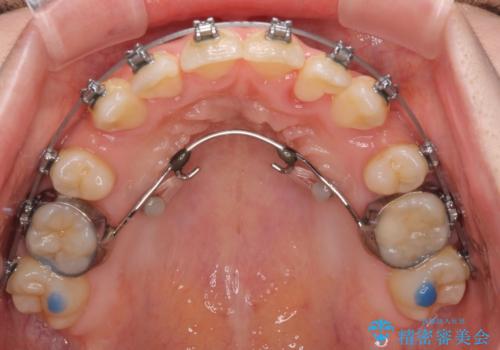

上顎前歯部はデコボコが強く、歯を並べるためのスペースが不足しているため、左右の第一小臼歯を抜歯することとしました。

また、抜歯して確保したスペースが不足してしまうのを防ぐため、補助装置を併用しています。

矯正治療の前に上下左右の親知らずの抜歯も行いました。